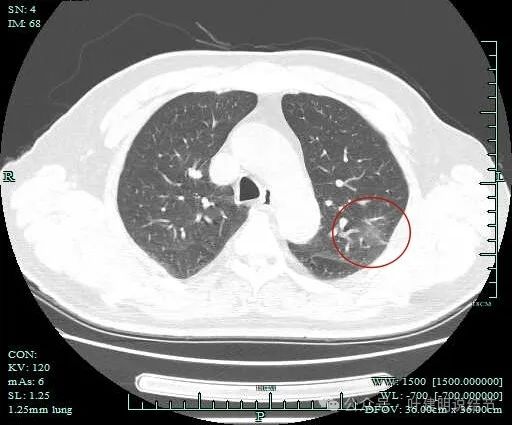

病灶出现,范围较大,密度较低,但轮廓较清楚。

病灶肺表面近,整体轮廓与边界清,表面不平,灶内有小空泡征。

灶内密度感觉欠均匀,虽然无明显实性成分。

灶内似有血管穿行与小空泡征,表面有细毛刺。